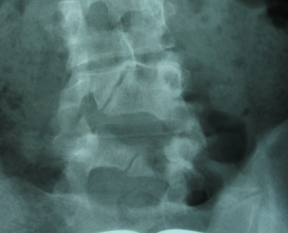

Estudio radiológico de columna vertebral en bipedestación

1) TRx AP de columna vertebral                                               2) Rx lateral de columna lumbar

HALLAZGOS RADIOLÓGICOS

• TRx AP de col. Vertebral

• Normal   49%

• Actitud escoliótica:   12%

• Anomalías de transición 10%

• Escoliosis   17%

• Dismetrías   12%